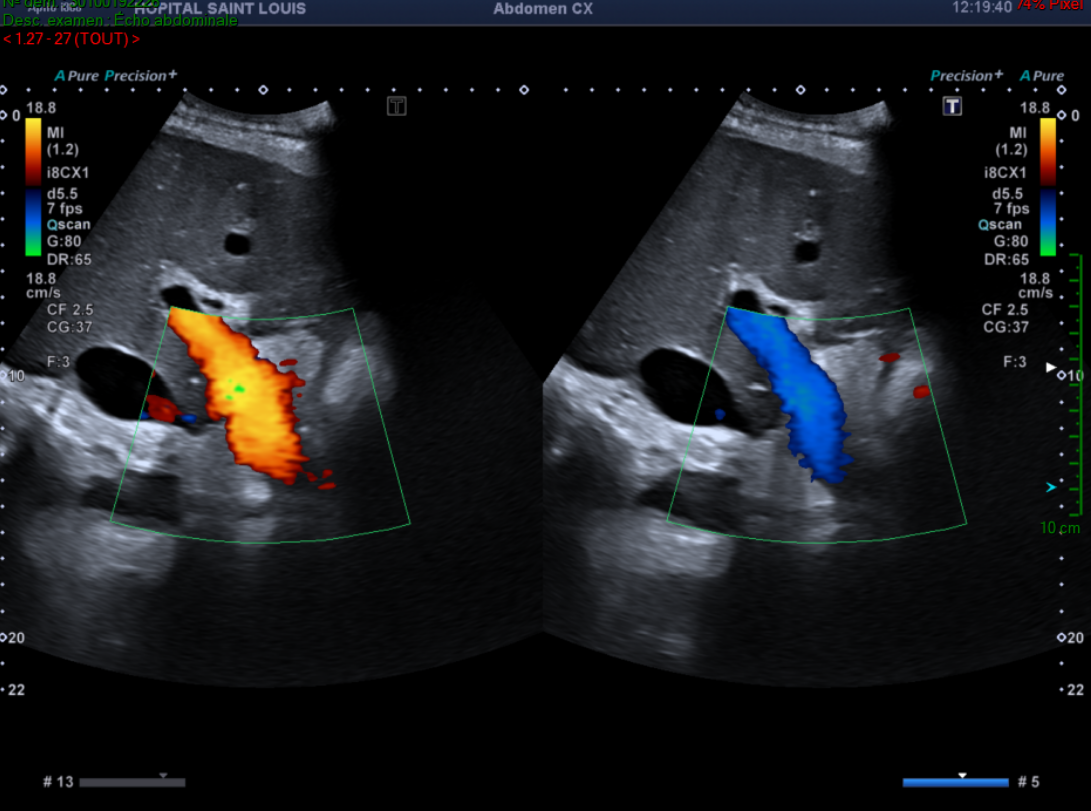

De plus, le flux du tronc porte attire son attention.

Il observe alors une alternance entre un flux hépatopète et hépatofuge au sein du tronc porte.

Un flux portal normal est dirigé vers le foie (hépatopète).

Pulsatilité du tronc porte